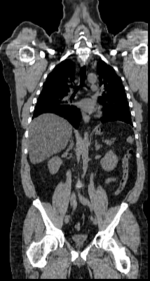

this is the fixed CT image. All images are aligned into this space this is the fixed PET image. All images are aligned into this space lleft this is the moving image. The transform is calculated by matching this to the reference image this is the moving image. The transform is calculated by matching this to the reference image

fixed image/target fixed image/target moving image moving image

• moving: CT: 0.98 x 0.98 x 5, 512 x 512 x 195; PET: 4.1 x 4.1 x 5 mm, 168 x 168 x 195